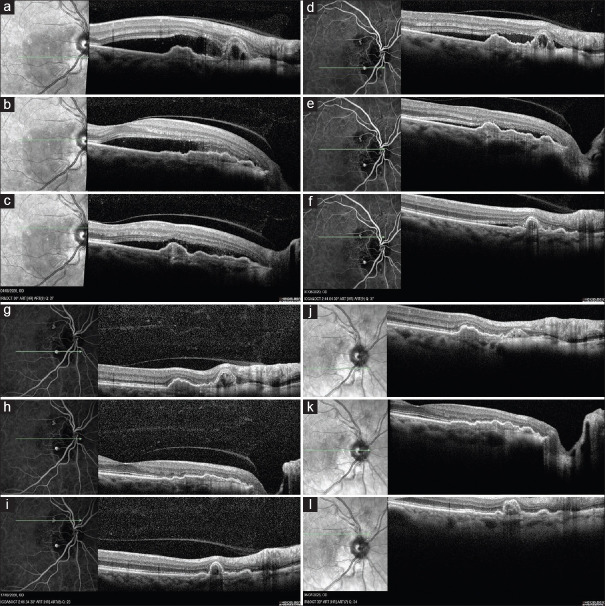

一位60岁的女性患有息肉样脉络膜血管病变(PCV),采用光动力疗法(PDT)治疗。治疗点很小(850µm),仅针对病变而不针对周围的血管网络。3天后,患者主诉视力严重受损,临床检查诊断为pdt所致急性渗出性黄斑病变(PAEM)。3天后的进一步检查一方面显示视网膜下积液已消退,但另一方面,确定PDT可能导致另外两个先前静止的PCV病变的激活。未应用其他治疗,并监测患者的临床状况。6周后复查,渗出现象完全消失,视力明显改善。三年过去了,病情依然稳定。我们的报告是文献中第一个描述PDT后小靶点(850µm) PAEM的病例,而没有其他报告表明pcv相关的PAEM可以在没有任何治疗的情况下自行消退。此外,PDT的应用伴随着两个先前不活跃的PCV病变的激活,这是先前未描述的不良反应。

A 60-year-old woman suffering from polypoidal choroidal vasculopathy (PCV) was treated with photodynamic therapy (PDT). The treatment spot was small (850 µm) and was targeted only against the lesion and not the surrounding vascular network. Three days later, she complained of severe visual impairment and the clinical examination set the diagnosis of PDT-induced acute exudative maculopathy (PAEM). Further examinations 3 days later demonstrated on the one hand that subretinal fluid had regressed, but on the other hand, it was identified that PDT possibly resulted in the activation of two other previously quiescent PCV lesions. No other treatment was applied, and the patient's clinical status was monitored. A new evaluation after 6 weeks, revealed the complete resolution of the exudative phenomena and the significant improvement of vision. Three years later, the condition remains stable. Our report is the first in the literature to describe a case of PAEM following PDT with a small target spot (850 µm), while no other report has demonstrated that PCV-associated PAEM may resolve spontaneously without any treatment. Moreover, the application of PDT was accompanied by the activation of two previously inactive PCV lesions, an adverse effect that has not been previously described.